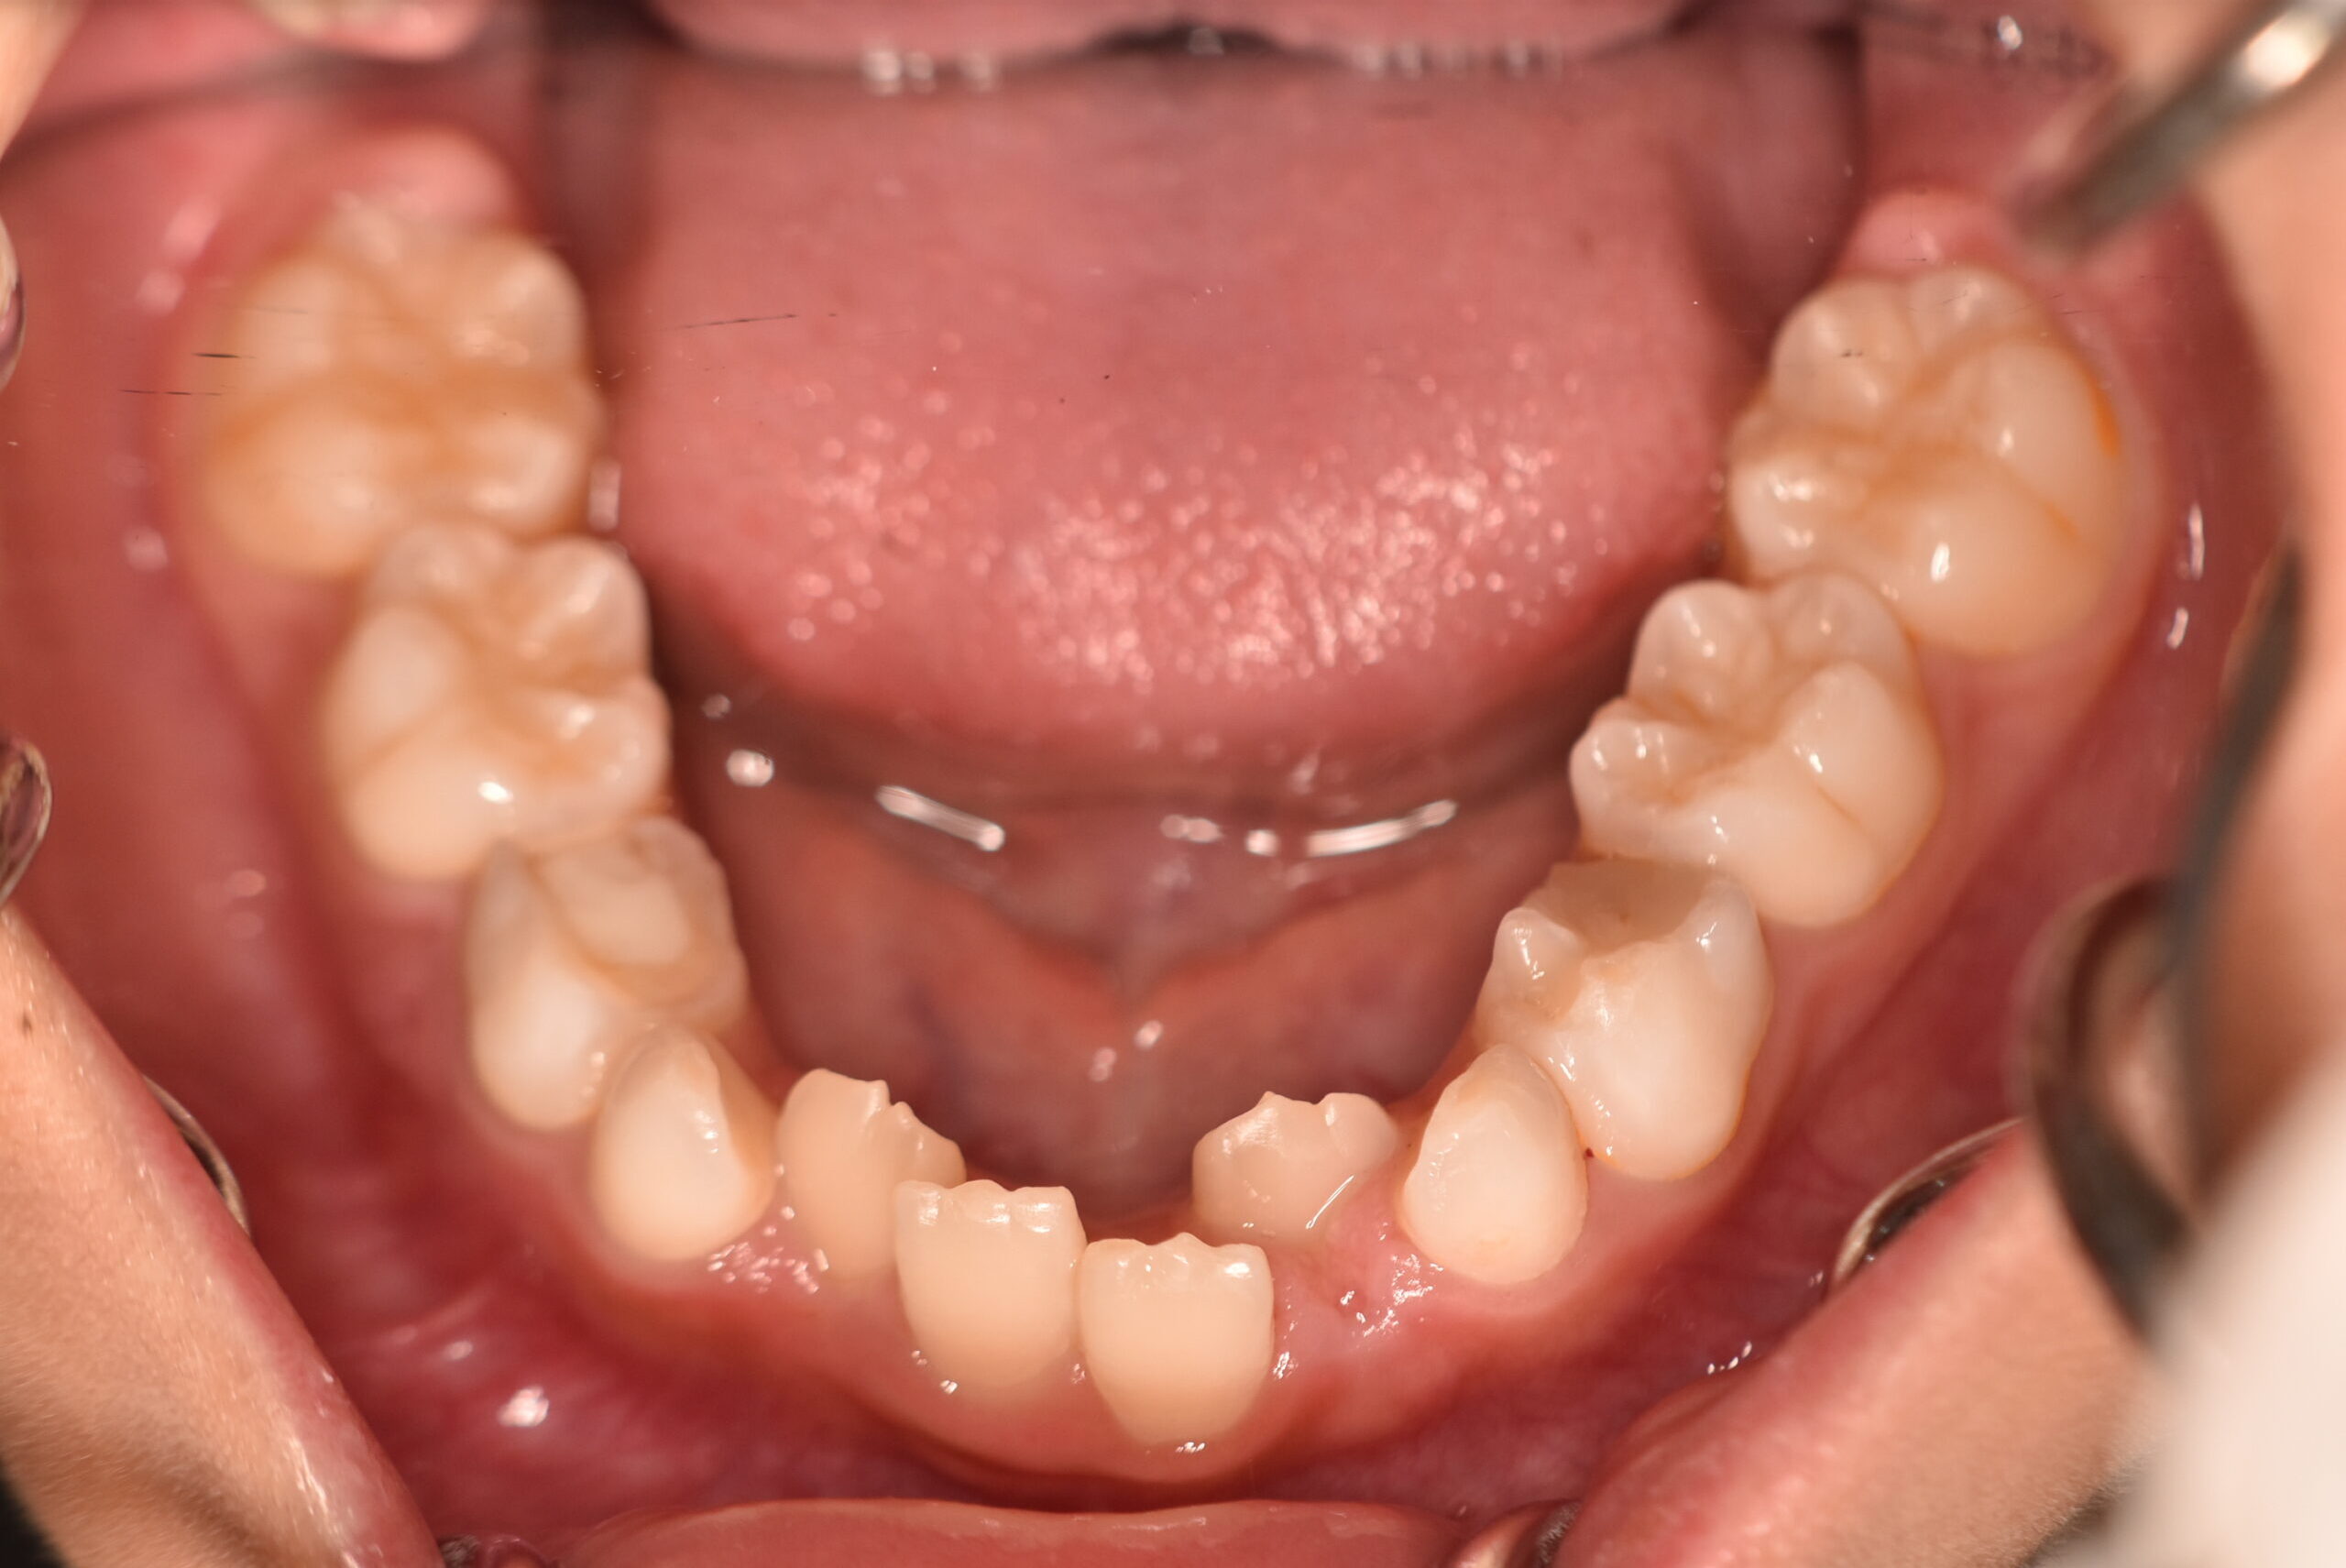

| 治療内容の詳細 | 初診時9歳3ヶ月の男児で、前歯が磨きにくく虫歯になりやすいことを気にされ来院されました。 検査の結果、前歯部叢生を伴うアングルⅠ級不正咬合と診断しました。 治療としてはマウスピース矯正(インビザラインファースト)で配列を行い、上下顎の側方拡大により永久歯の萌出スペースを確保しました。 治療期間は、1年6ヶ月でした。 今後、永久歯(側方歯)の生え変わりまで経過観察を行います。 |